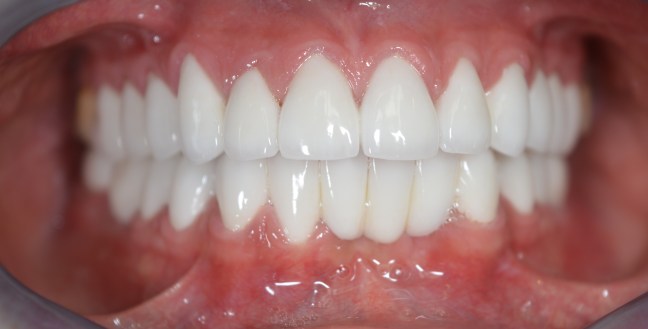

Felső fogatlan állcsont korszerű ellátása: felső teljes fogatlanság kezelése 6 implantátumon rögzített fix híddal. Multi unit tengelykorrekciós fejek, csavarosan rögzített híd.

Implantátum: Nobel Biocare.

Hídpótlás anyaga: cirkónium vázra égetett porcelán.

A választott fogszín: A1.

A protetikai munka elkészülésének ideje: 8 munkanap.